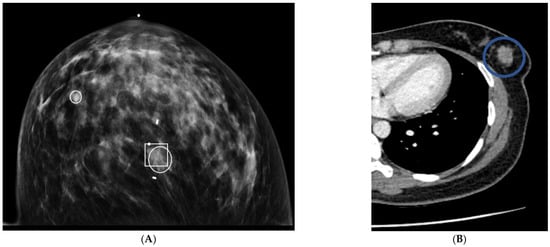

Figure 5. Craniocaudal mammographic image reveals clustered left breast microcalcifications that were recommended for biopsy (A). Contrast chest CT in axial projection on the same day reveals a 20 mm mass with an average HU of 61 (B). Biopsy results were invasive breast cancer.

Figure 4. Right upper outer quadrant microcalcifications on craniocaudal mammography were recommended for biopsy (A). Axial chest CT performed 128 days prior to the mammogram recommended biopsy for a 20 mm right upper outer quadrant mass (B). Biopsy results at the time of mammography were ductal carcinoma in situ.

3.4. Calcifications

Microcalcifications were identified on twenty mammograms, and biopsy was recommended in five (25%). In total, 2/20 (10%) patients with micro-calcifications on mammography had breast cancer. No micro-calcifications were identified on CT. In patients who had micro-calcifications on mammography, CT correctly diagnosed two true positive nodules (Figure 4 and Figure 5), one of which was ductal carcinoma in situ and the other was invasive breast cancer. The remaining eighteen patients with microcalcifications on mammography were correctly identified as normal on chest CT.

We were concerned about the inability of CT scan to recognize micro-calcifications. Twenty patients had microcalcifications on mammography, of which two were cancer. CT correctly diagnosed these two patients because a nodule was seen on CT in the area of microcalcifications. A nodule was not identified on mammography for these two patients. The findings suggest that, like MRI, CT may diagnose the most clinically relevant microcalcifications, but further investigation is needed [17].